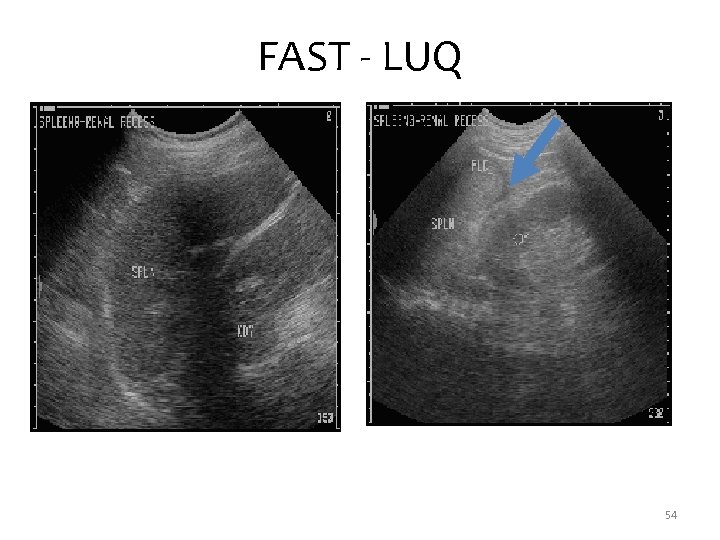

FAST – Left Upper Quadrant • View between the spleen and kidney • Another dependent place that fluid collects • Also see diaphragm in this view 53

FAST - LUQ 54